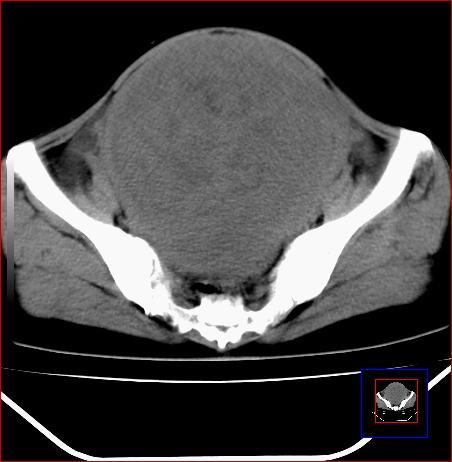

标题: CT15141:子宫肌瘤还是卵巢肿瘤 [打印本页]

标题: CT15141:子宫肌瘤还是卵巢肿瘤

腹部包块1年余,近两月明显增大,月经量多

病灶呈实性包块,边界清晰,似与子宫分界不清,考虑:子宫肌瘤

子宫体积增大,内密度不均匀。边缘清晰。考虑子宫肌瘤。

子宫体积增大,内密度不均匀。边缘清晰。考虑子宫肌瘤可能性大。